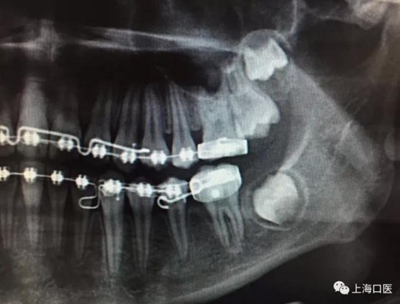

這是上海武廣增正畸工作室接診的一例非常規(guī)拔牙矯治病例,患者女性,初診年齡14歲。LL6殘冠拔除。LL7近中平移取代LL6,我們上傳了該患者一組下頜磨牙近中平移連續(xù)矯治過程的正畸X線片,與正畸界朋友分享。

來源:武廣增 上海口醫(yī)